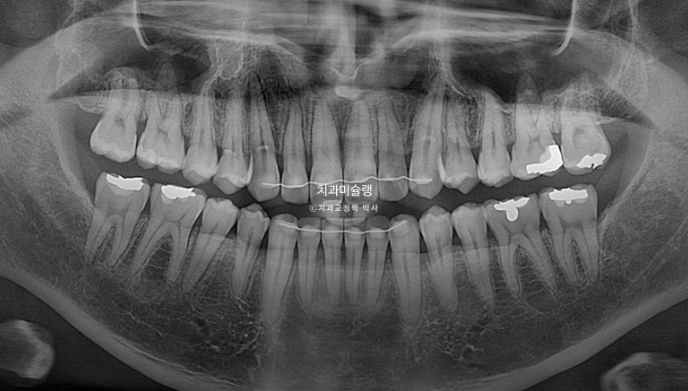

교정 후 치근흡수는 없고 뿌리 정렬상태도 좋습니다.